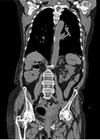

Post radical nephrectomy presenting with skull metastasis

We present the case of an 83-year-old female who underwent right radical nephrectomy for renal cell carcinoma (RCC). Despite negative surgical margins, the patient presented with a skull metastasis six years post radical nephrectomy. This case highlights the importance of...